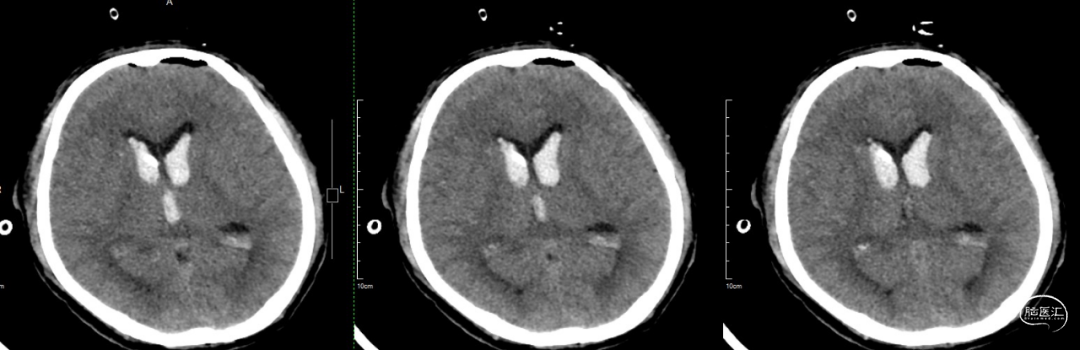

术后一周CT:脑室积血基本吸收。